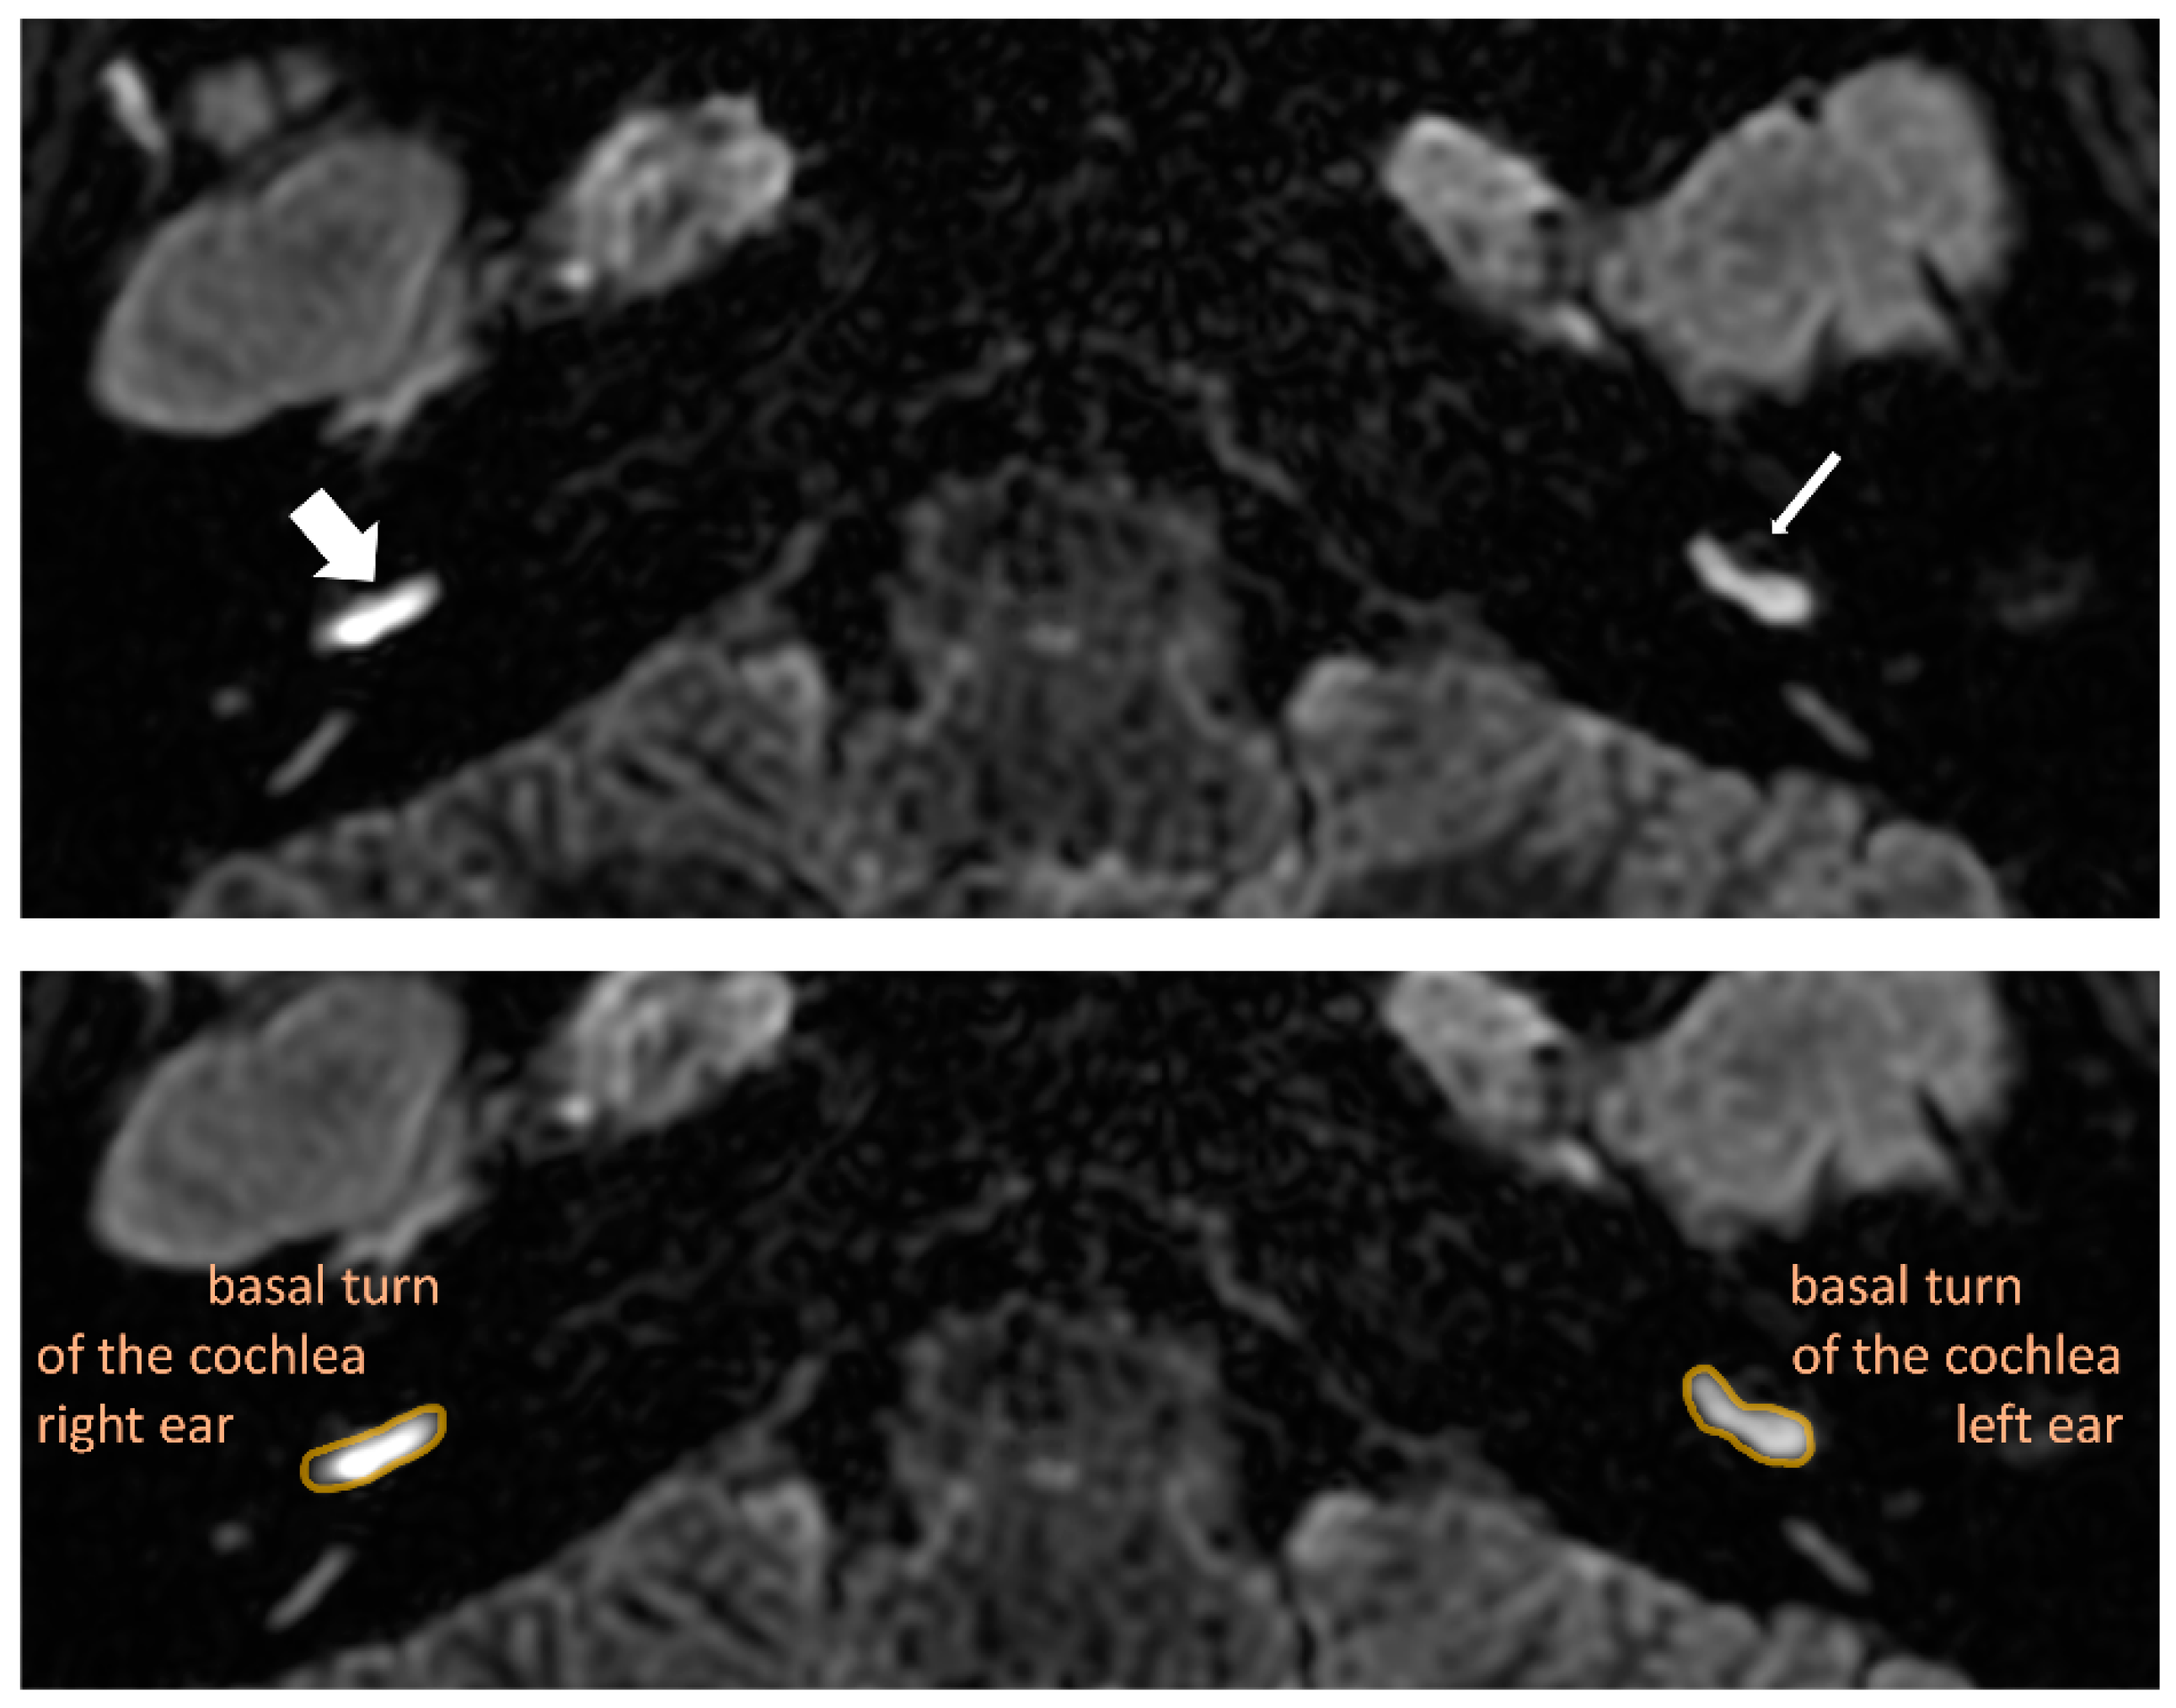

2.3. Magnetic Resonance Imaging Procedure and Analysis